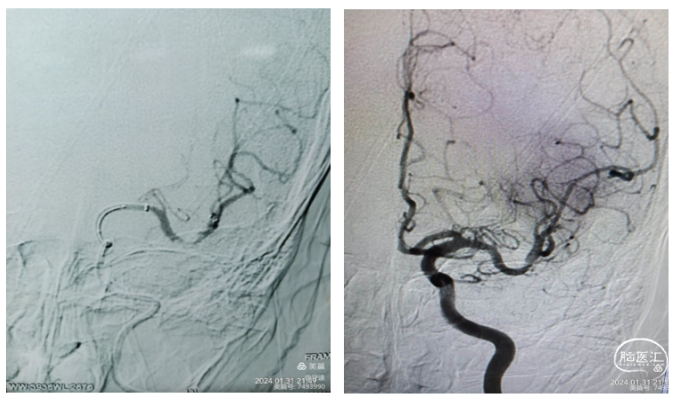

再次将支架置于M1远端,在支架铆定下跟进中间导管越过了C6迂曲到达M1段,抽拉结合2次取栓。通过中间导管进行二次抽吸后造影显示:血管再通,M1远端仍有小节段狭窄,但血流达到3级。结束手术。

建立通路和抽吸导管输送的插图。Nueron MAX长鞘开始应置于颈动脉360°环的近端,以避免发生颈动脉夹层(图1)。沿着微导丝-微导管-抽吸导管组成的三同轴系统,可使长鞘安全地沿360°环向远端推进,通过C1段环状迂曲部位,同时并不会强行改变这种血管迂曲的状态。随后在长鞘高到位支撑下容易将抽吸导管继续向M1段的血栓部位推进。下图。